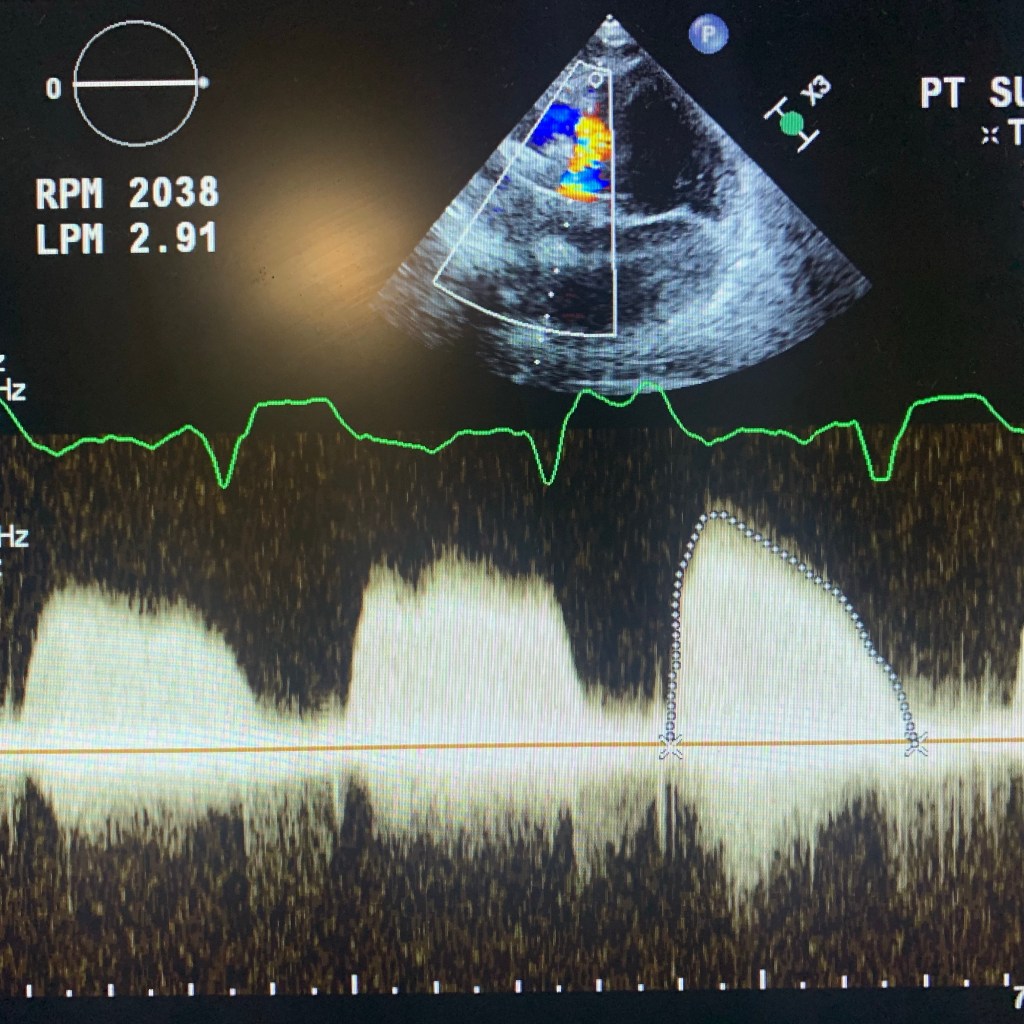

🔘 during RAMP studies: theres no LV dimention change with increased pump support/RPM

Below are a few images and videos of RVAD and changes in RAMP study I did recently